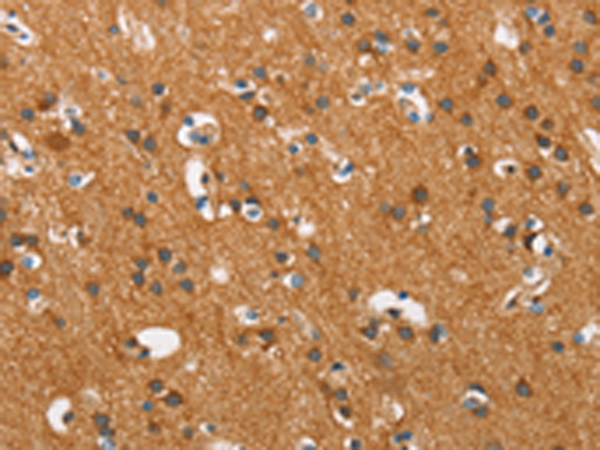

分类: 科研抗体货号: P11572别名: PD1; NACP; PARK1; PARK4应用: IHC反应种属: Human, Mouse, Rat